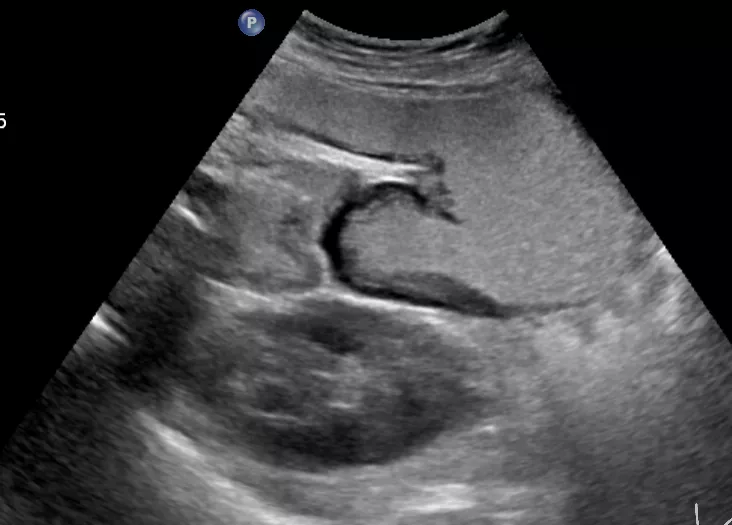

胃癌

什么情况下不能做超声造影呢?